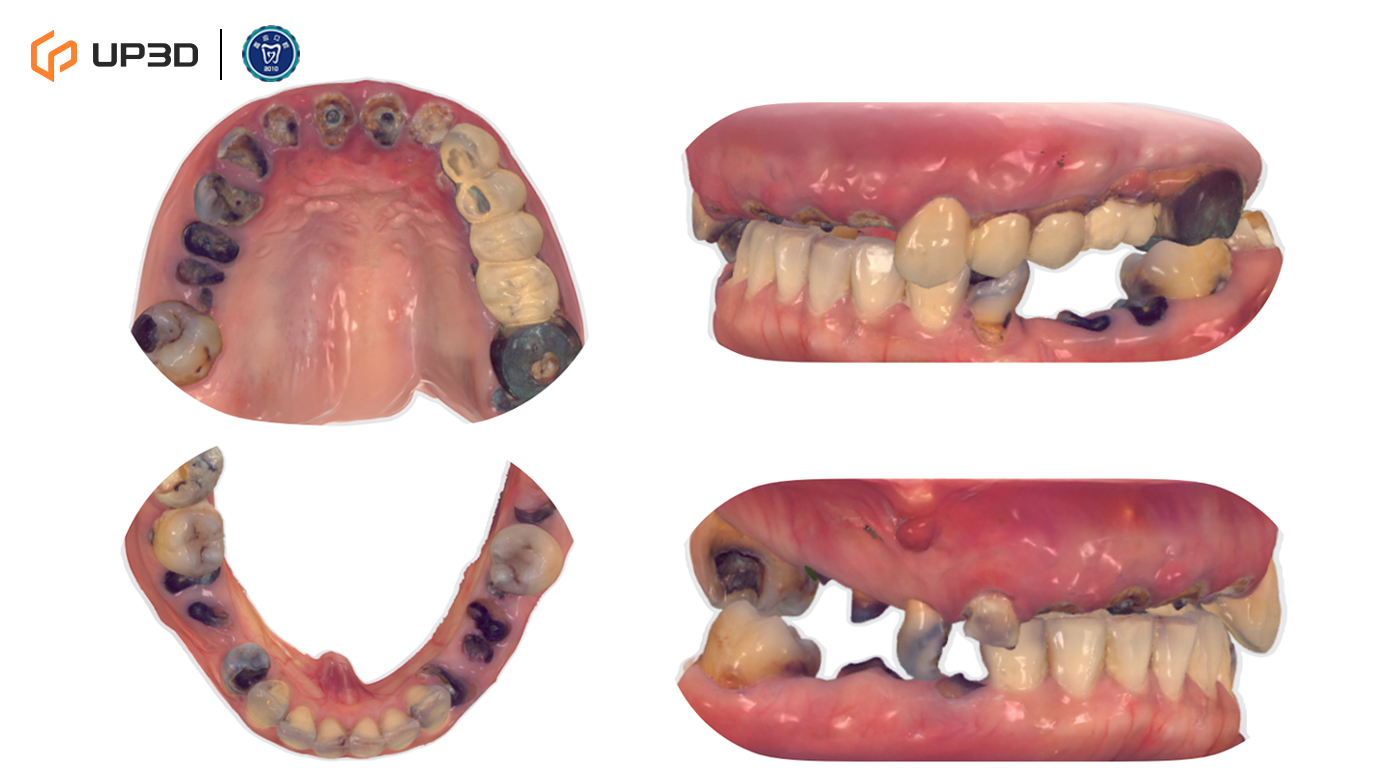

2.1 Intraoral Findings and Intraoral Scan Assessment

A digital intraoral scan (IOS) was used to capture maxillary and mandibular models. Clinical findings included multiple missing teeth, disordered dentition, and occlusal collapse with reduced facial support. Bone volume was limited in certain regions. The 3D scan clearly presented tooth morphology, soft tissue contours, and occlusal relationships—providing accurate data for subsequent digital implant planning.